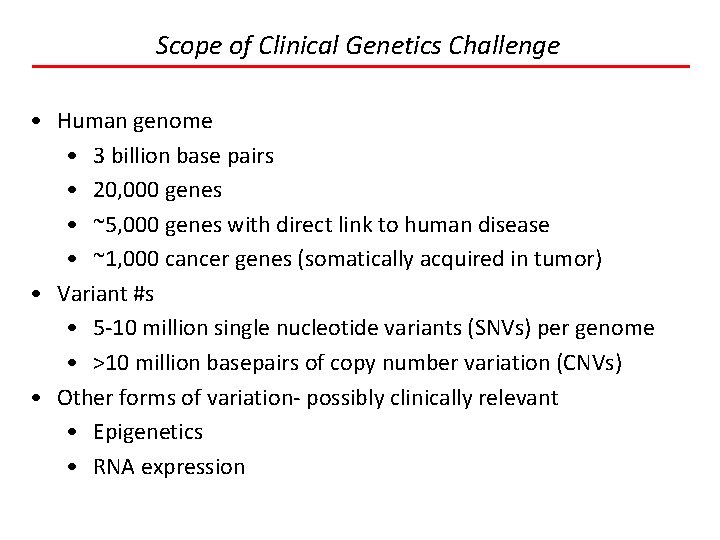

Scope of Clinical Genetics Challenge • Human genome • 3 billion base pairs • 20, 000 genes • ~5, 000 genes with direct link to human disease • ~1, 000 cancer genes (somatically acquired in tumor) • Variant #s • 5 -10 million single nucleotide variants (SNVs) per genome • >10 million basepairs of copy number variation (CNVs) • Other forms of variation- possibly clinically relevant • Epigenetics • RNA expression